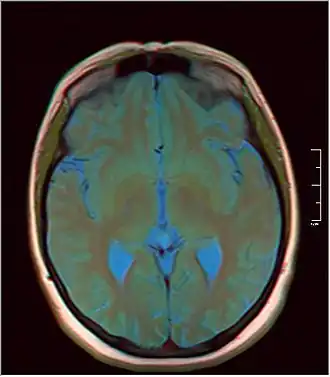

MRI axial in false color

MRI axial in false color -